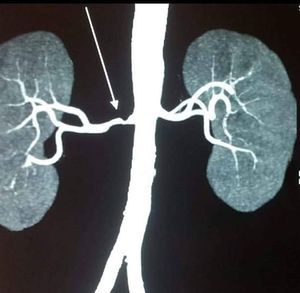

Dx please??

Stenosis of arteria renalis maybe?

Renal artery stenosis

Unilateral Renal Artery Stenosis (could be due to atherosclerosis or unilateral fibromuscular dysplasia)